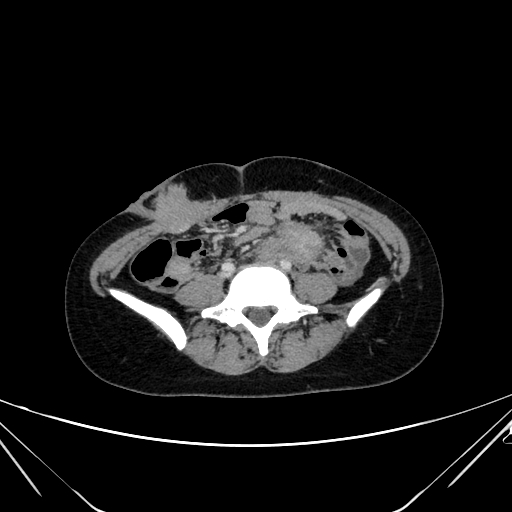

Findings Her entire large bowel was studded with multiple polyps.The rectum and sigmoid had larger polyps as compared to the smaller rest of the bowel which has numerous smaller lesions(Image 1).An ultrasound of her breast was undertaken for the right breasy mass lesion .The ultrasound showed a rather circumscribed lesion in the upper inner quadrant of the right breast splaying fibres of the pectoralis (Black arrowheads in Image 2 ).The lesion was clinically firm to hard and showed no appreciable vascularity on Doppler (Image 3). A USG guided biopsy of the lesion was undertaken which showed spindle cells that were positive for CD99 ,SMA,Desmin and Negative for S100, pan CK, CK 5/6, p63 and CD117,CD 34 . Ki 67 index was less than 3%.(Image 4) . ?eta Catenin showed strong diffuse nuclear positivity(Image 4) . Diagnosis of a spindle cell neoplasm, morphology and immunoprofile favoring Desmoid fibromatosis was given on pathology . Patient eventually underwent prophylactic pancolectomy.She presented a few months post surgery with irregular soft tissue density masses at site of surgical incision on the right rectus (Image 5) and a large intra abdominal mesenteric mass causing distortion and dense bowel adhesions (Image 6). These were diagnosed as fibromatosis on imaging